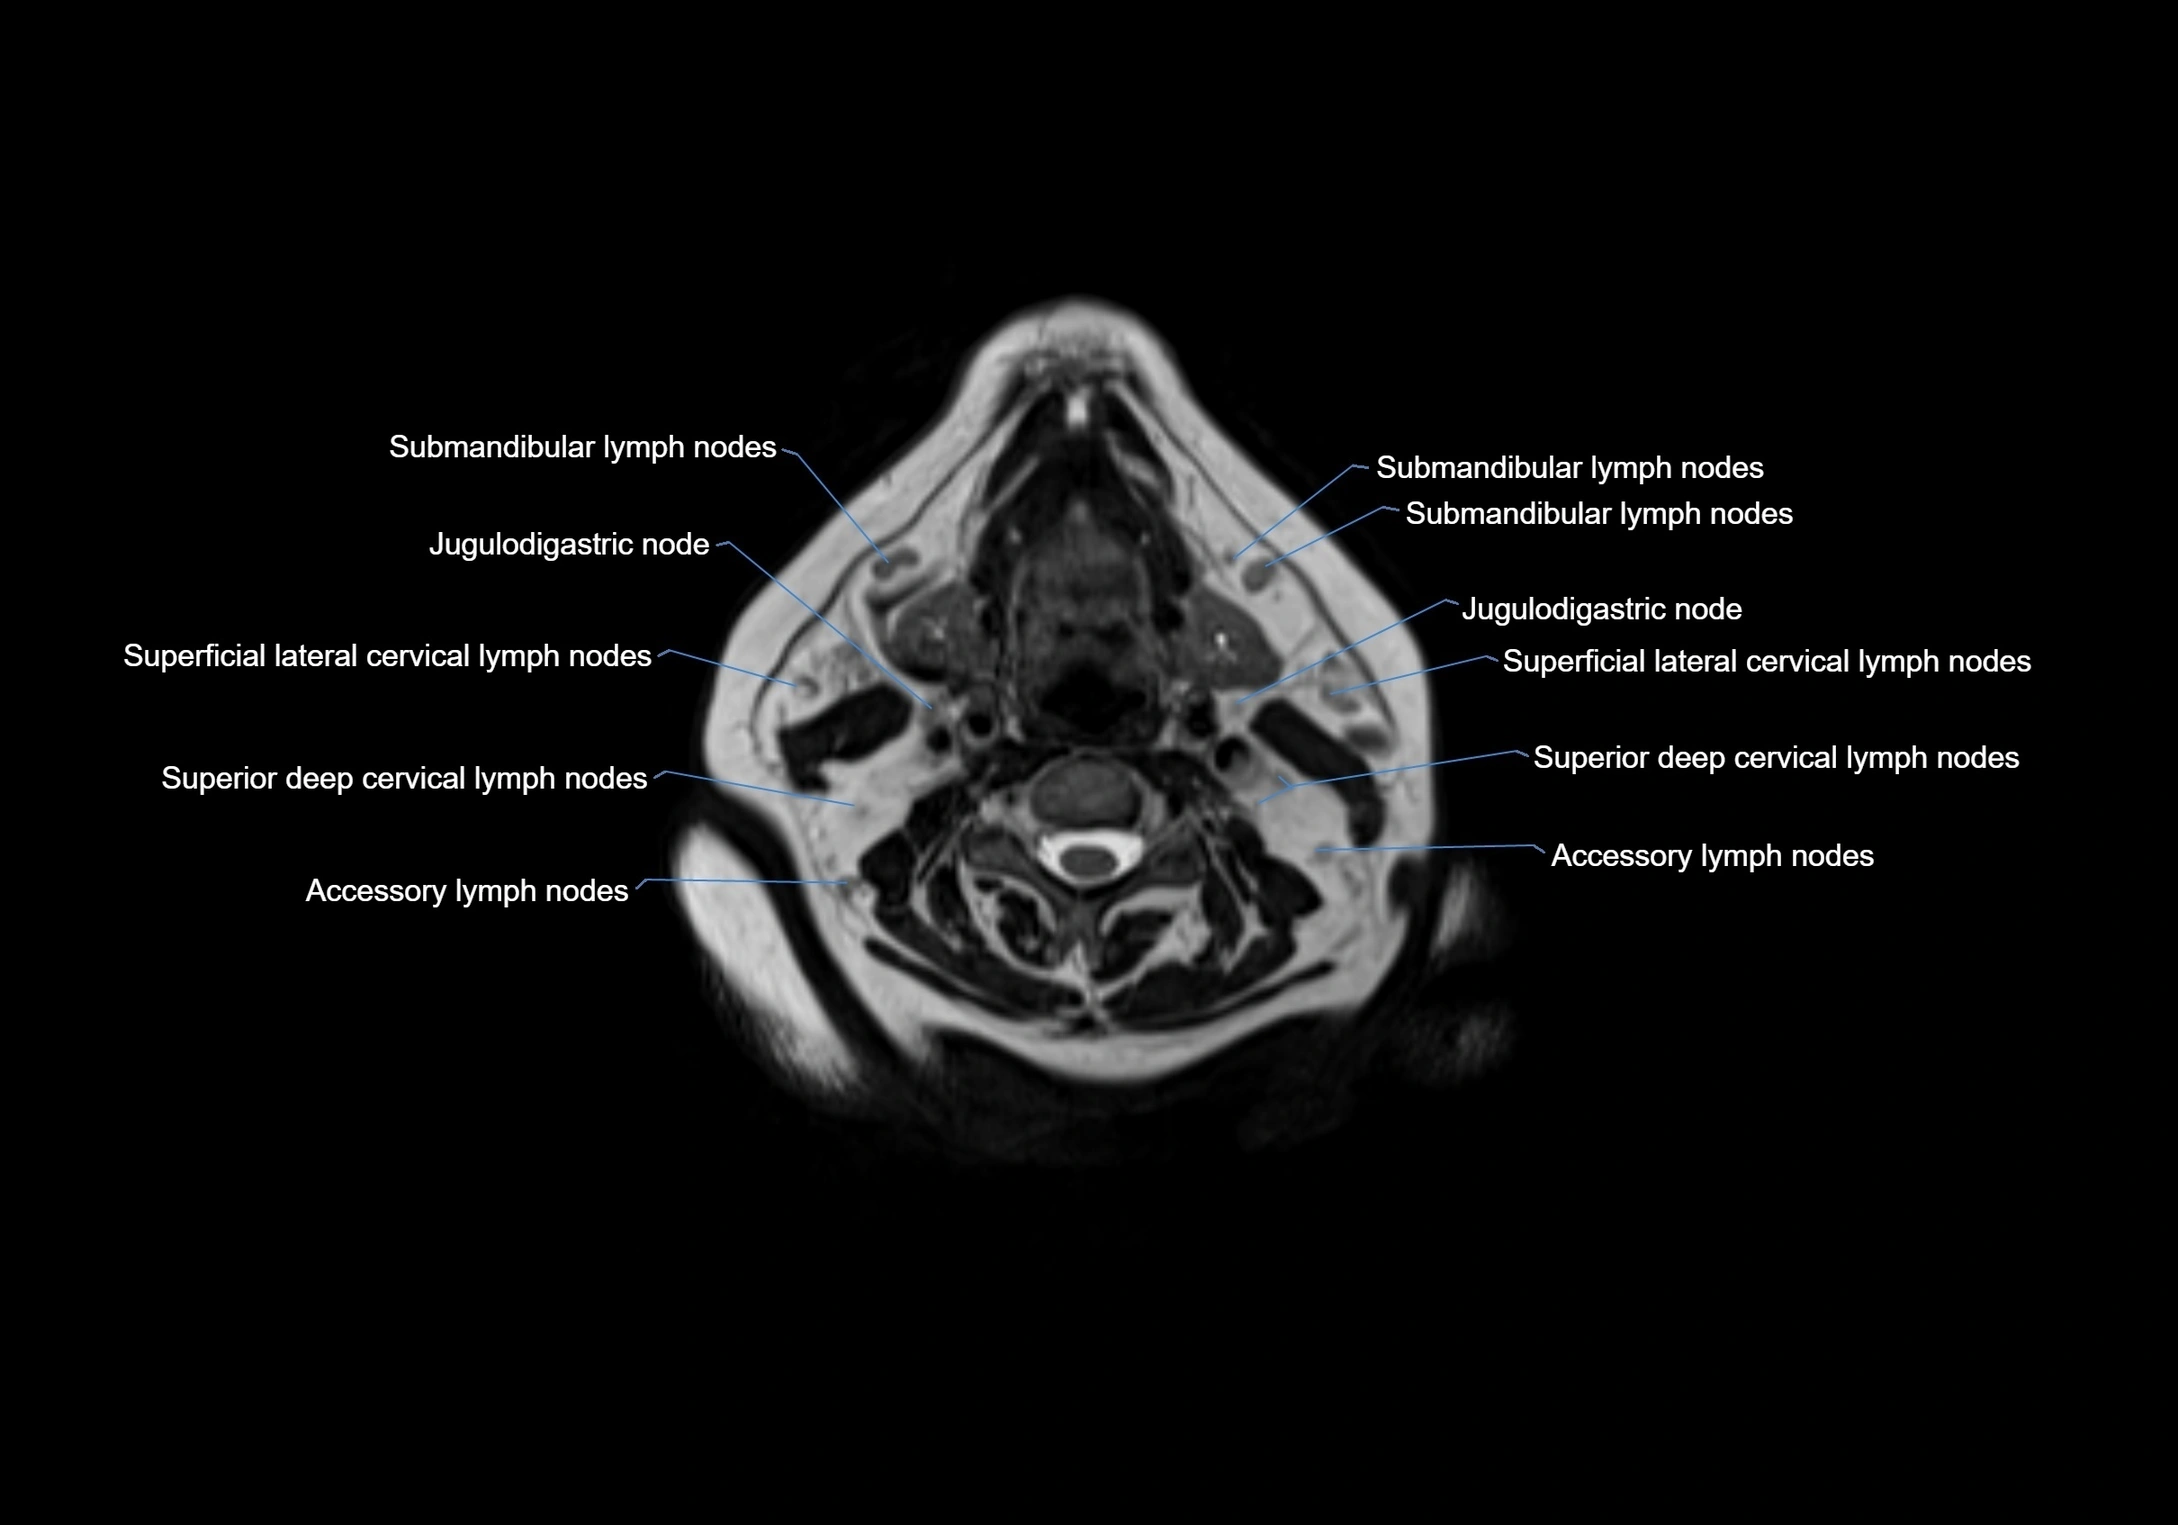

Accessory lymph nodes

Accessory lymph nodes are small, secondary lymph nodes located along the main facial and cervical lymphatic chains, often adjacent to primary lymph nodes, such as preauricular, submandibular, or occipital nodes. They are typically less than 5 mm in diameter, embedded within subcutaneous fat or connective tissue, and may be variable in number and location. These nodes provide additional filtration and immune surveillance for lymph collected from the face, scalp, and neck regions. Accessory lymph nodes are usually non-palpable in healthy individuals but may enlarge in response to infection, inflammation, or metastasis, making them clinically significant.

Location

• Found along primary lymph node chains, including preauricular, submandibular, parotid, and occipital regions

• Embedded in subcutaneous fat or superficial fascia, often lateral or posterior to primary nodes

• Variable in number; may occur unilaterally or bilaterally, depending on individual anatomy

MRI images

image